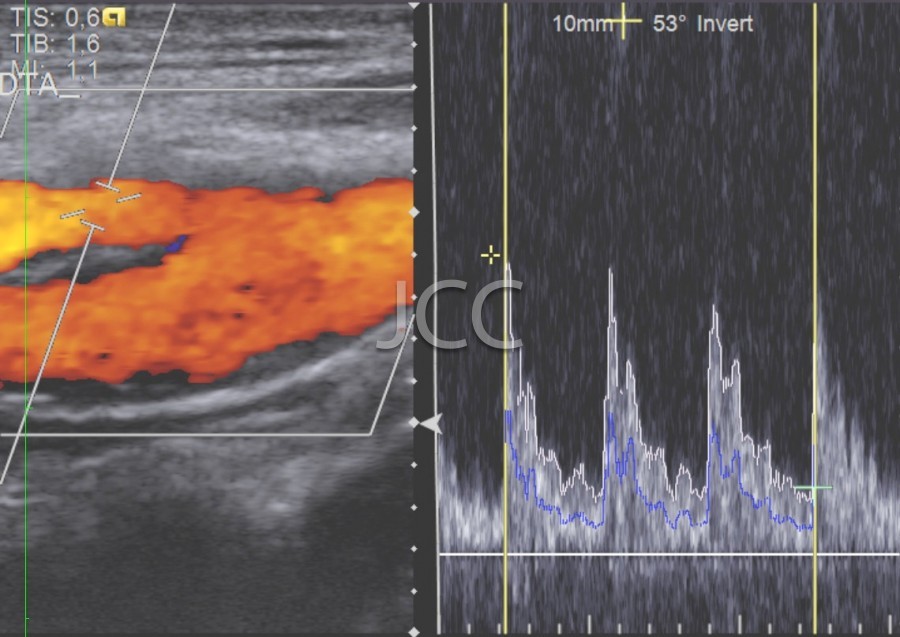

Ecografia - Ecografia Vascular - Doppler

A Ecografia constitui um método mais acessível permitindo de modo simples e rápido a avaliação dos órgãos do corpo humano incluindo o fígado, vias biliares, vesícula, pâncreas, rins, bexiga e próstata, bem como órgãos de menores dimensões como a tiróide, parótidas e estruturas musculares.

Constitui uma óptima técnica para guiar a realização de biópsia. Quando associada ao Doppler permite o estudo das estruturas vasculares arteriais e venosas de modo dinâmico.